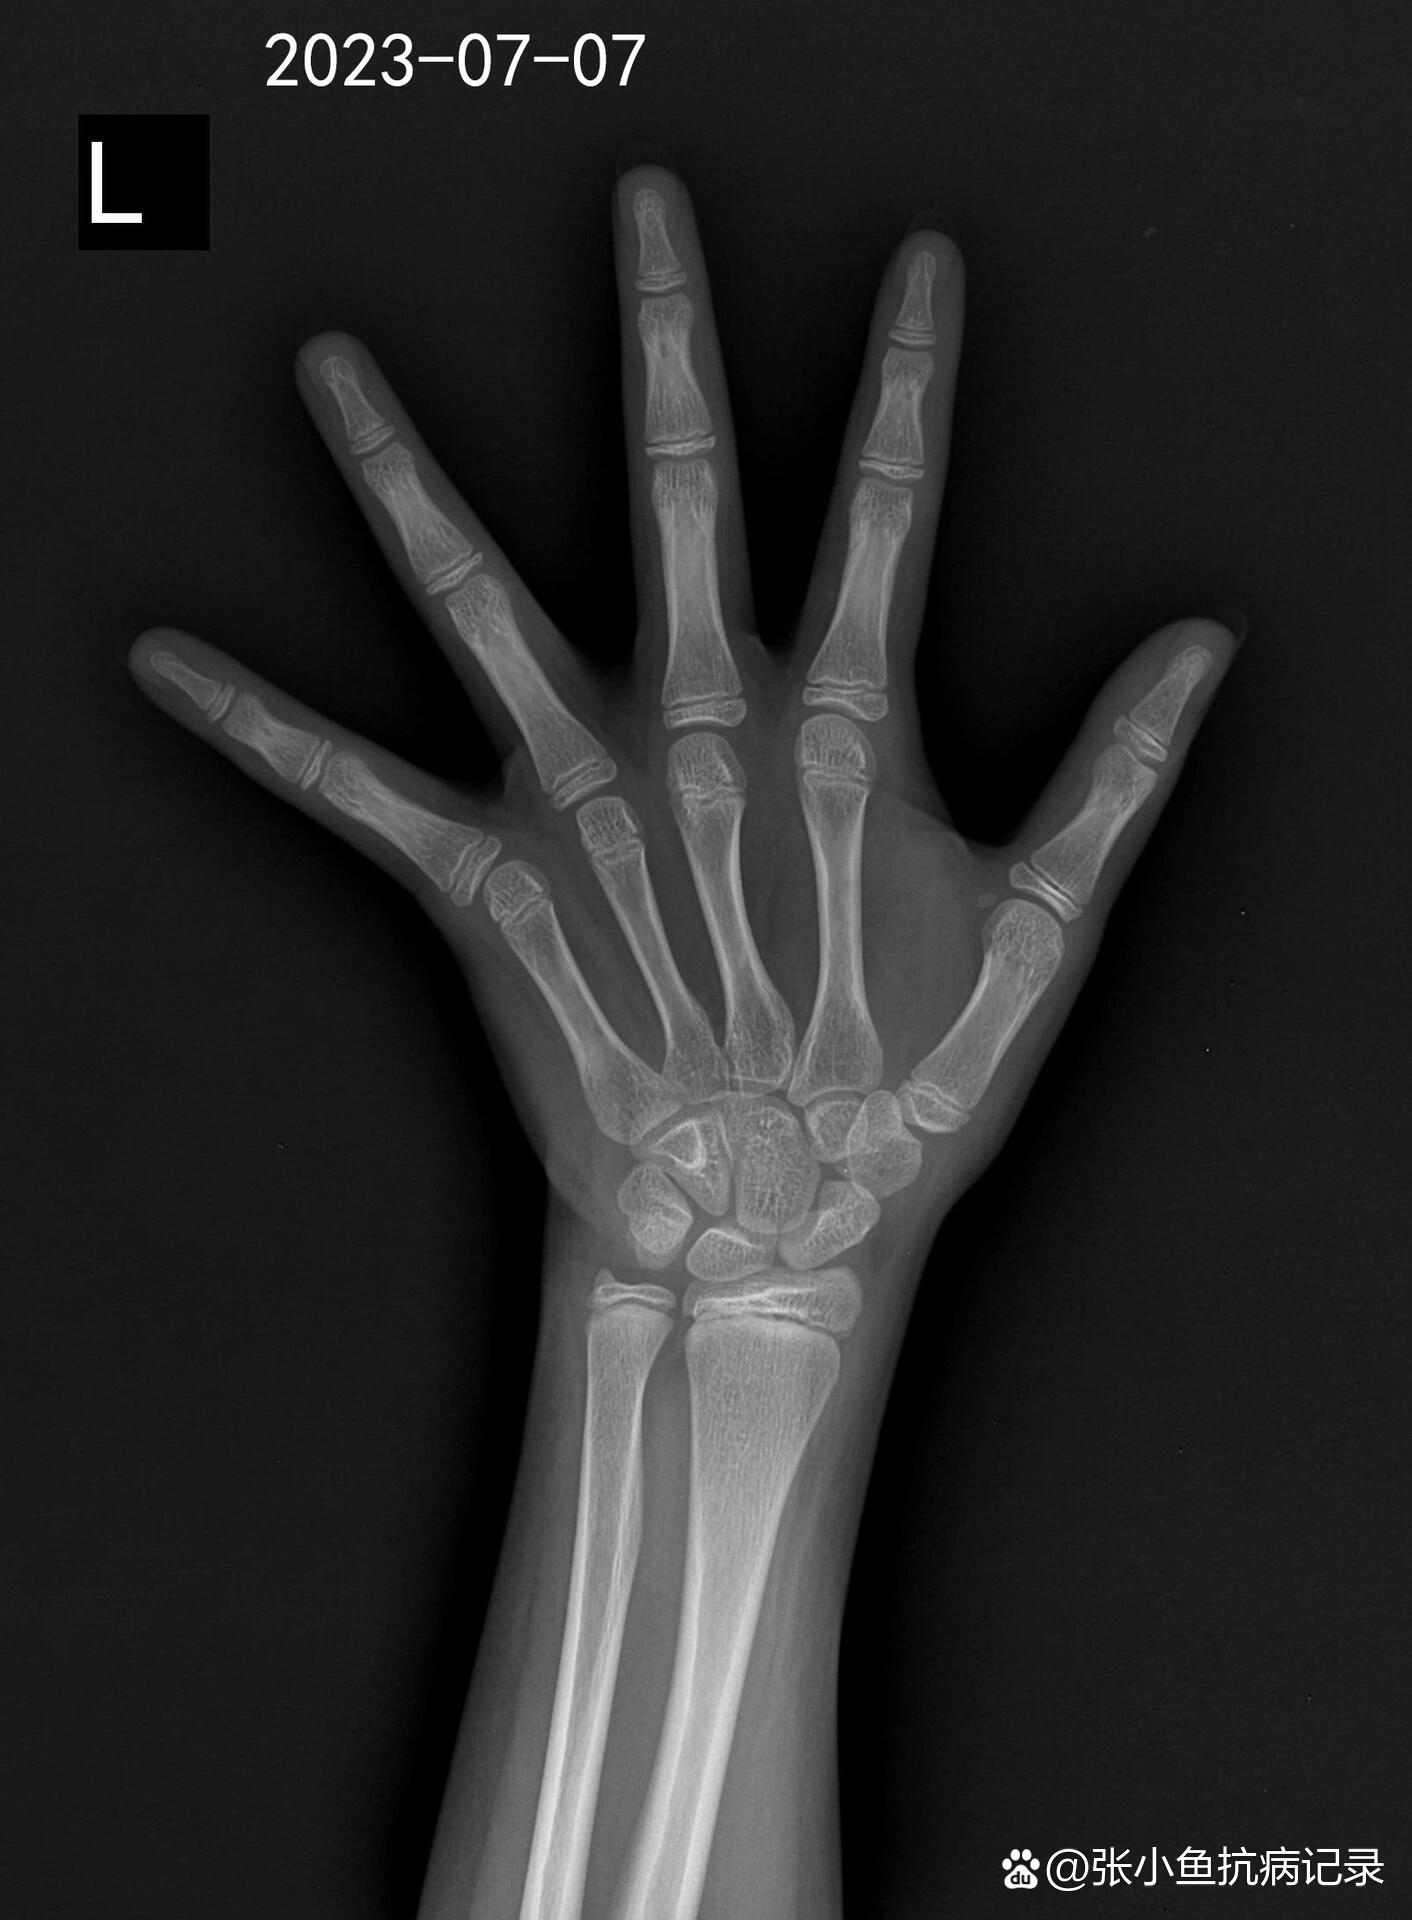

骨龄知识全解析:助力孩子健康成长

图片尺寸1080x1260